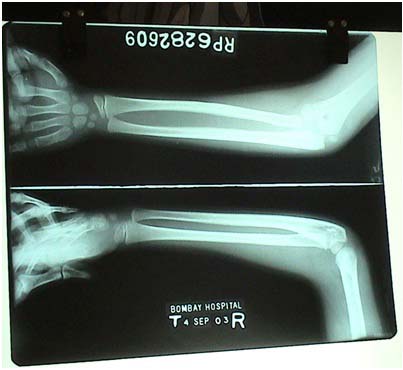

At present he has chronic leg pains over the shin of the leg.

This kid's case was studied extensively and he was prescribed Ficus religiosa 30 in May 2003. After about 3-4 months he showed significant improvement in his leg pains and his religious disposition was modified too, he was not inclined much now.